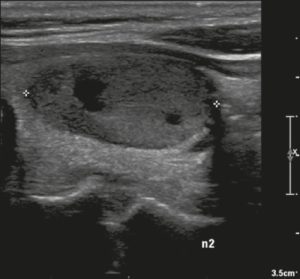

Ở đây, chúng tôi cung cấp các ví dụ minh họa việc áp dụng thực tế hệ thống ACR TI-RADS (Hình 18, 19, 20, 21). Các chú thích dưới hình mô tả chi tiết các mục đã được đánh giá và hiển thị điểm số trong ngoặc đơn.

Hình 18. Hình ảnh nhân giáp dạng đặc (2 điểm), đồng âm (1 điểm), rộng hơn cao (0 điểm), có bờ trơn láng (0 điểm) và không có các ổ tăng âm hay bóng lưng (0 điểm). Do đó, tổng điểm là 3 điểm và mức độ nguy cơ được phân loại là TR3.